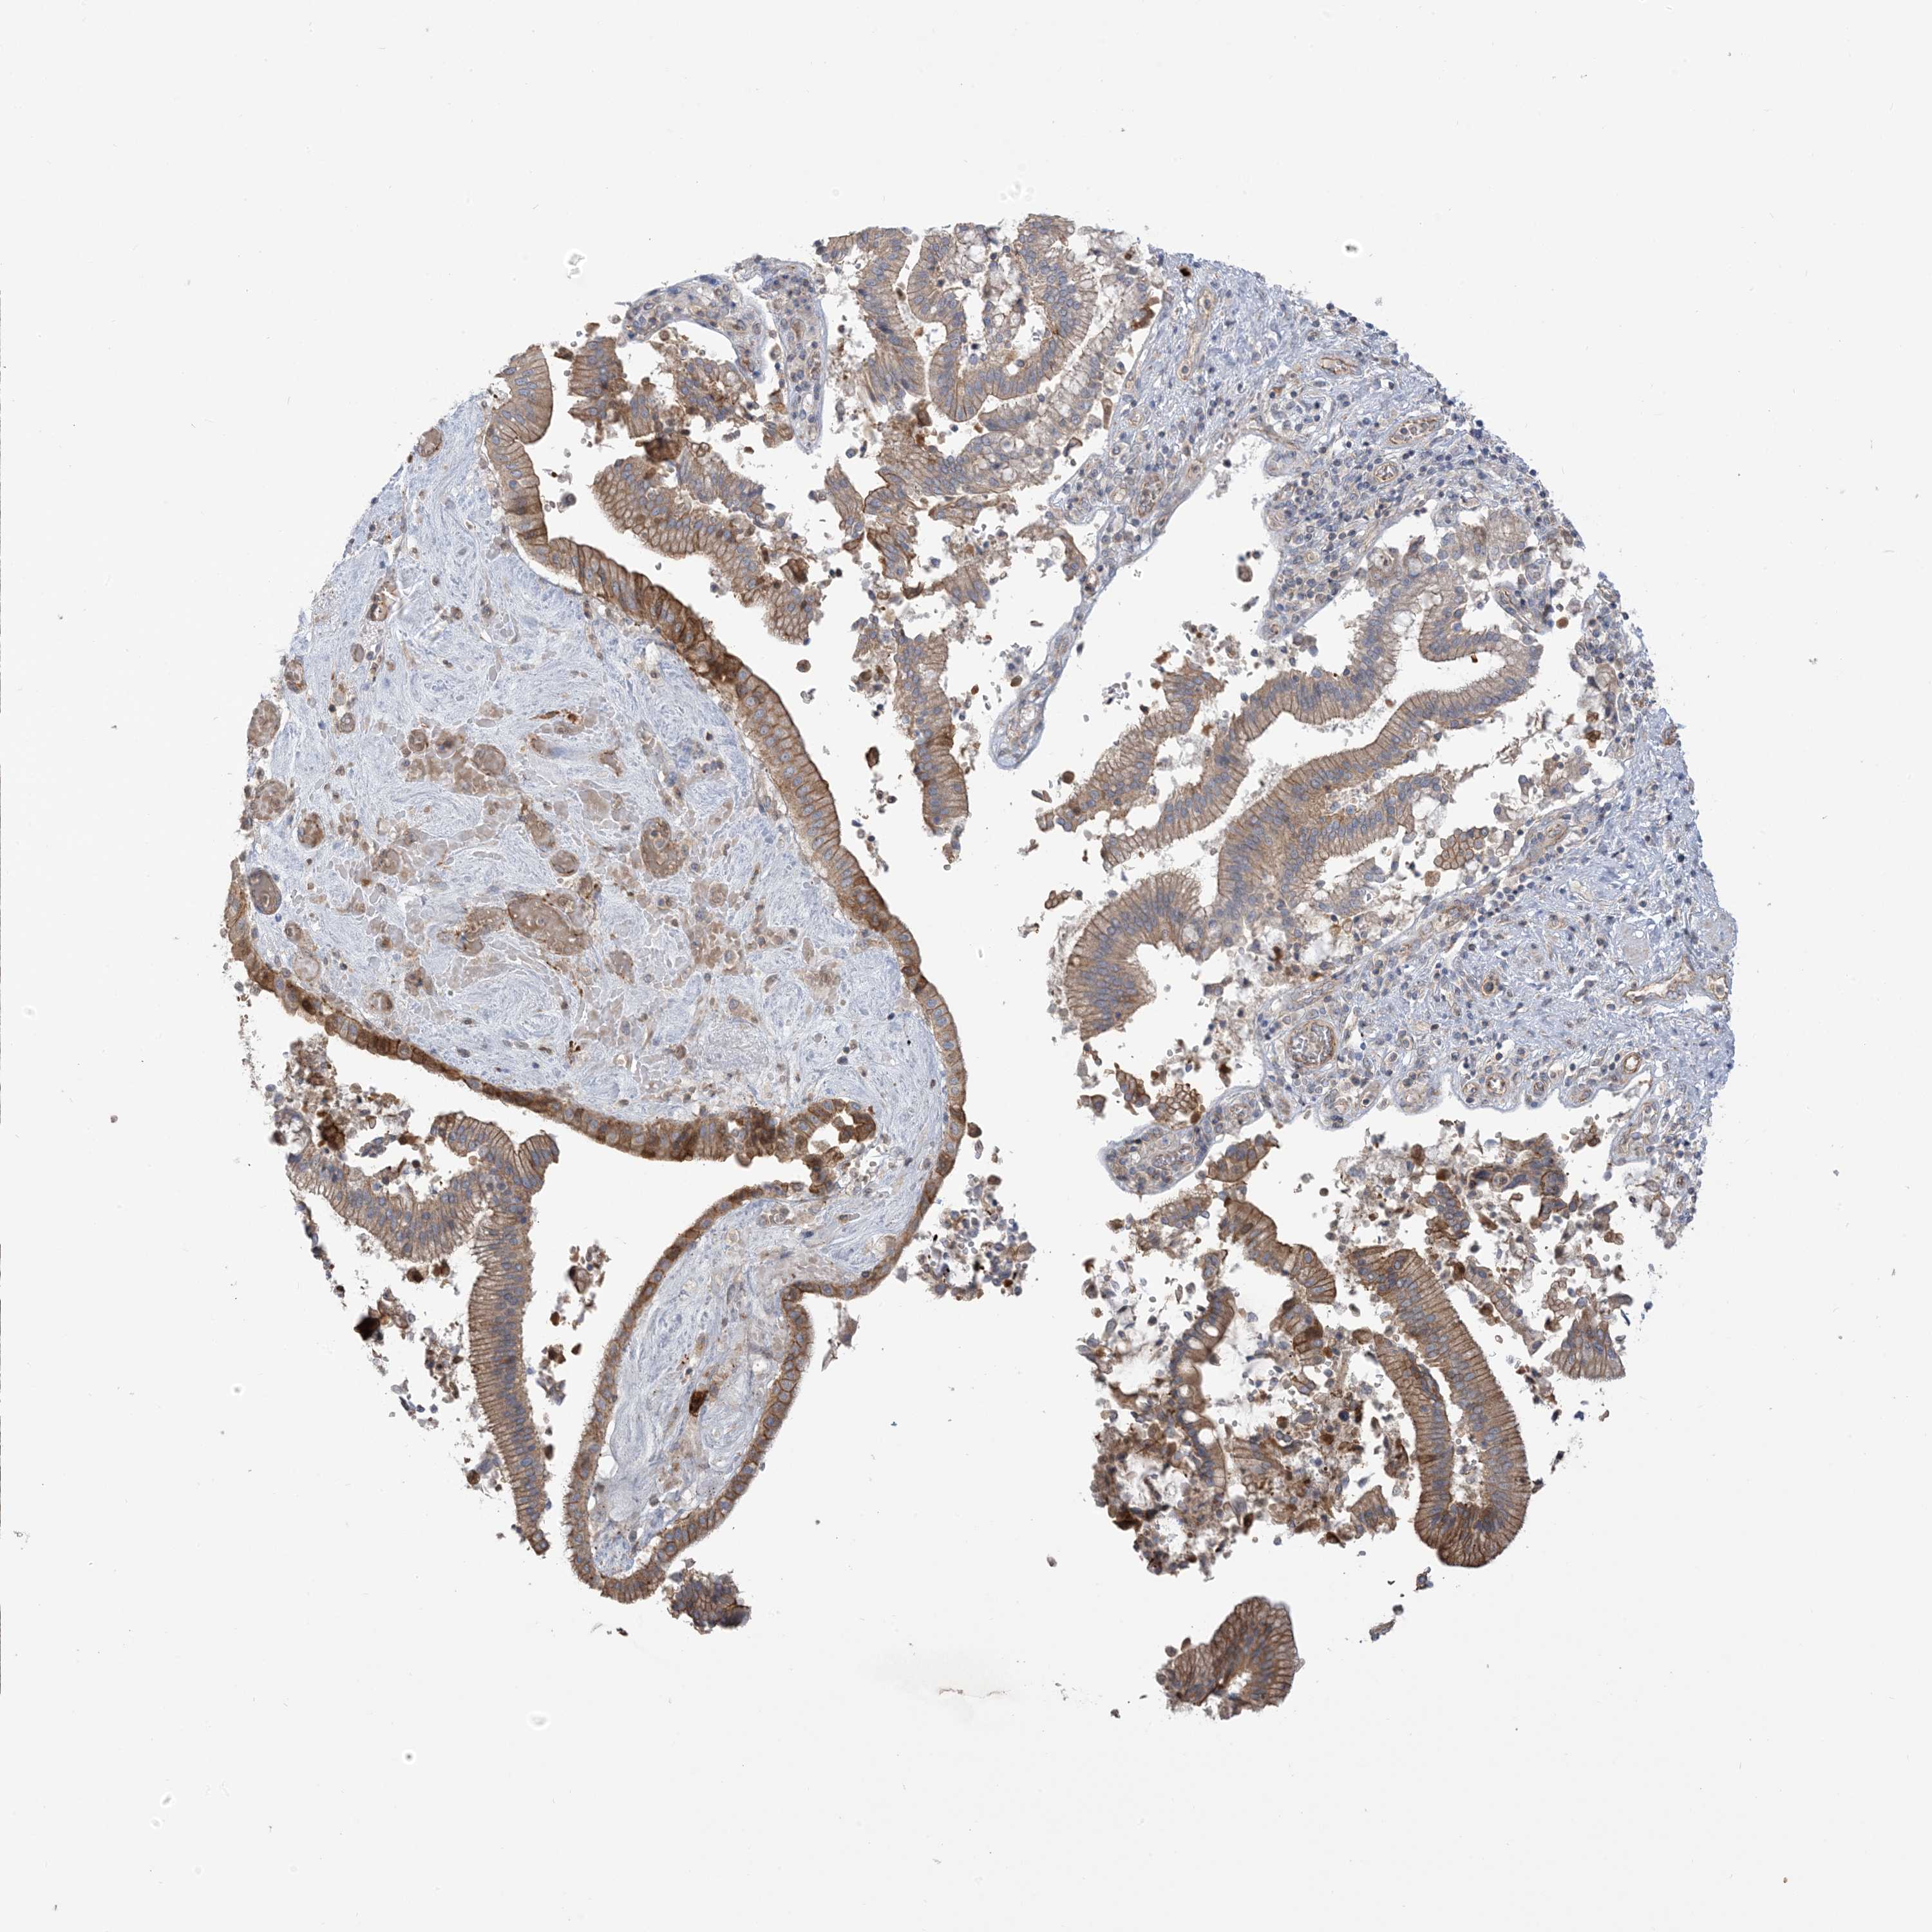

PANCREATIC CANCER - Protein expressioni

A mouse-over function shows sample information and annotation data. Click on an image to view it in a full screen mode. Samples can be filtered based on level of antibody staining by selecting one or several of the following categories: high, medium, low and not detected. The assay and annotation is described here.

Note that samples used for immunohistochemistry by the Human Protein Atlas do not correspond to samples in the TCGA dataset.

Antibody stainingi

Antibody staining in the annotated cell types in the current human tissue is reported as not detected, low, medium, or high, based on conventional immunohistochemistry profiling in selected tissues. This score is based on the combination of the staining intensity and fraction of stained cells.

Each image is clickable and will lead to virtual microscopy that enables deeper exploration of all samples and also displays staining intensity scores, fraction scores and subcellular localization as well as patient and tissue information for each sample.

Antibody HPA032024

Antibody HPA032025

Staining

High

Medium

Low

Not detected

Intensity

Strong

Moderate

Weak

Negative

Quantity

>75%

75%-25%

<25%

None

Location

Nuclear

Cytoplasmic/membranous

Cytoplasmic/membranous,nuclear

Adenocarcinoma, NOS